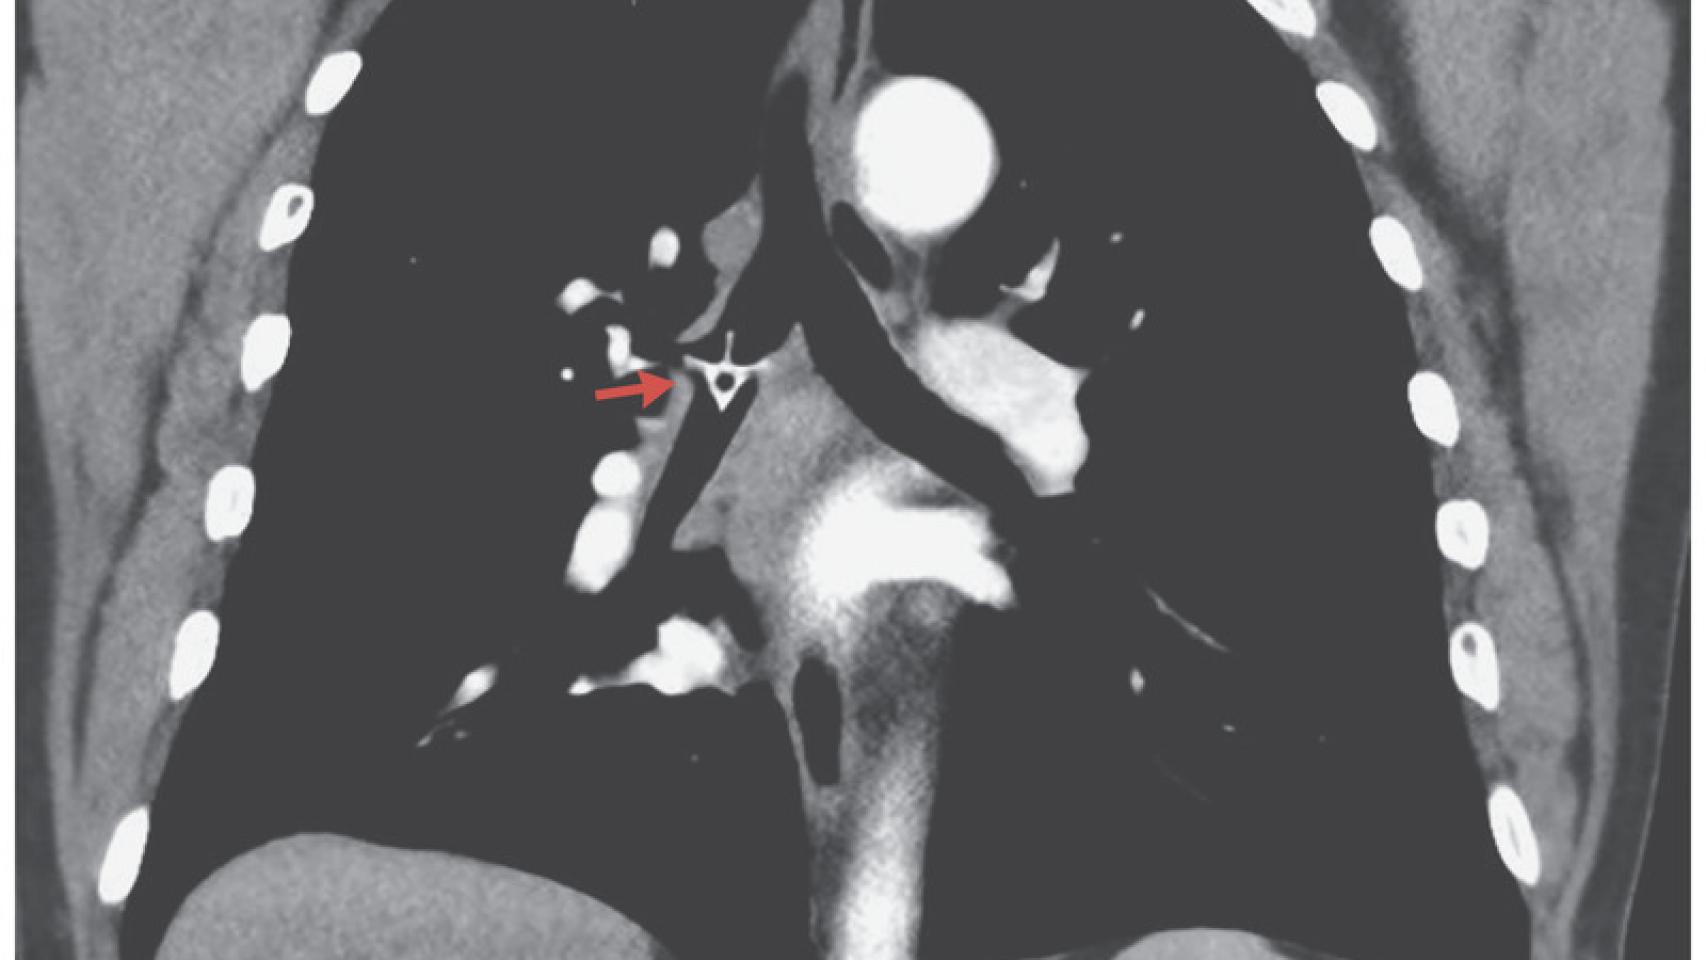

Sin embargo, tras el paso de cinco días, el hombre volvió de nuevo a urgencias: tenía fiebre, dificultad respiratoria y producía un sonido sibilante y agudo con cada respiración. Por ello, conociendo el dato de la visita anterior, los médicos que le atendieron le realizaron directamente un estudio de tomografía computerizada (TAC), en el cual sí se pudo vislumbrar un hueso de pollo en su bronquio derecho, la vía que une la tráquea con uno de los pulmones. El área donde se encontraba el hueso no dejaba pasar el aire correctamente, aunque no producía una obstrucción grave.

Por tanto, no es raro afirmar que el diagnóstico de casos como este pueden llegar a retrasarse más de lo que uno pueda llegar a imaginar, sobre todo si se trata de objetos pequeños que no llegan a producir un bloqueo significativo de las vías respiratorias. Asimismo, cabe destacar que alrededor del 80% de los cuerpos extraños no llegan a ser visibles en las radiografías de tórax, algo que hace difícil su diagnóstico, ya que es la prueba inicial que suele realizarse en estos casos.